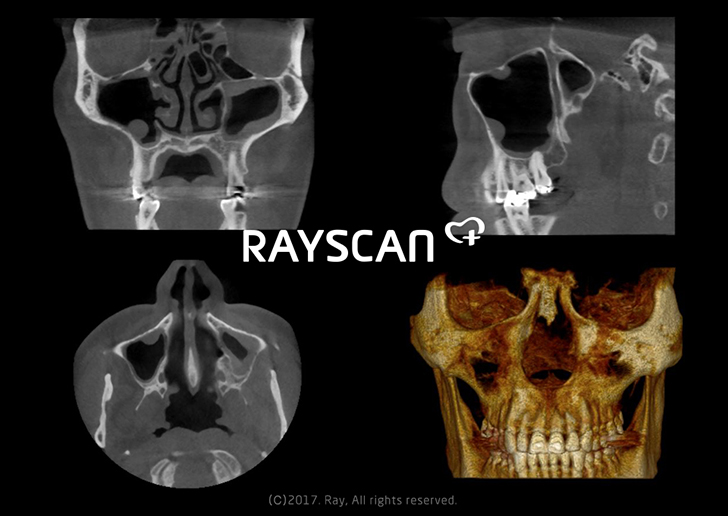

Crystal clear 3D CBCT images of sinuses can easily be acquired by our RAYSCAN m+.

The clear 3D images from RAYSCAN m+ visualize detailed morphological information from patients’ sinus, ear, airway, bones and soft tissues. The...

RAYSCAN m+ is the unique 2-in-1 imaging solution, combining Cone Beam CT and Digital Radiography, especially designed for otorhinolaryngology and plastic...